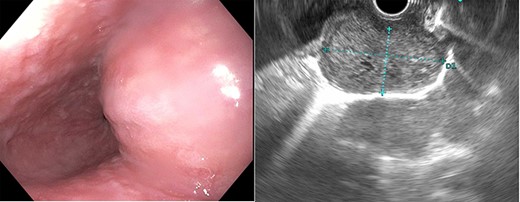

The patient is a 67-year-old male with a history of atrial fibrillation and hyperlipidemia who presented with several months of dysphagia to solids. The endoscopic evaluation revealed a ~4 × 2.3 cm submucosal lesion arising from the muscularis propria in the distal esophagus (Fig. 1). The lesion was 2 cm proximal to the GE junction and intermittently disappearing with peristaltic contractions. The lesion was biopsied and showed low-grade GIST with 1–3 mitoses per high power field and was CD 117 positive. Computerized tomography (CT) scan showed a right esophageal mass without evidence of local invasion (Fig. 2).

Esophagogastroduodenoscopy showed an esophageal prominence 2 cm above the GE junction with endoscopic ultrasound confirming 39.8 × 23.2 mm mass.